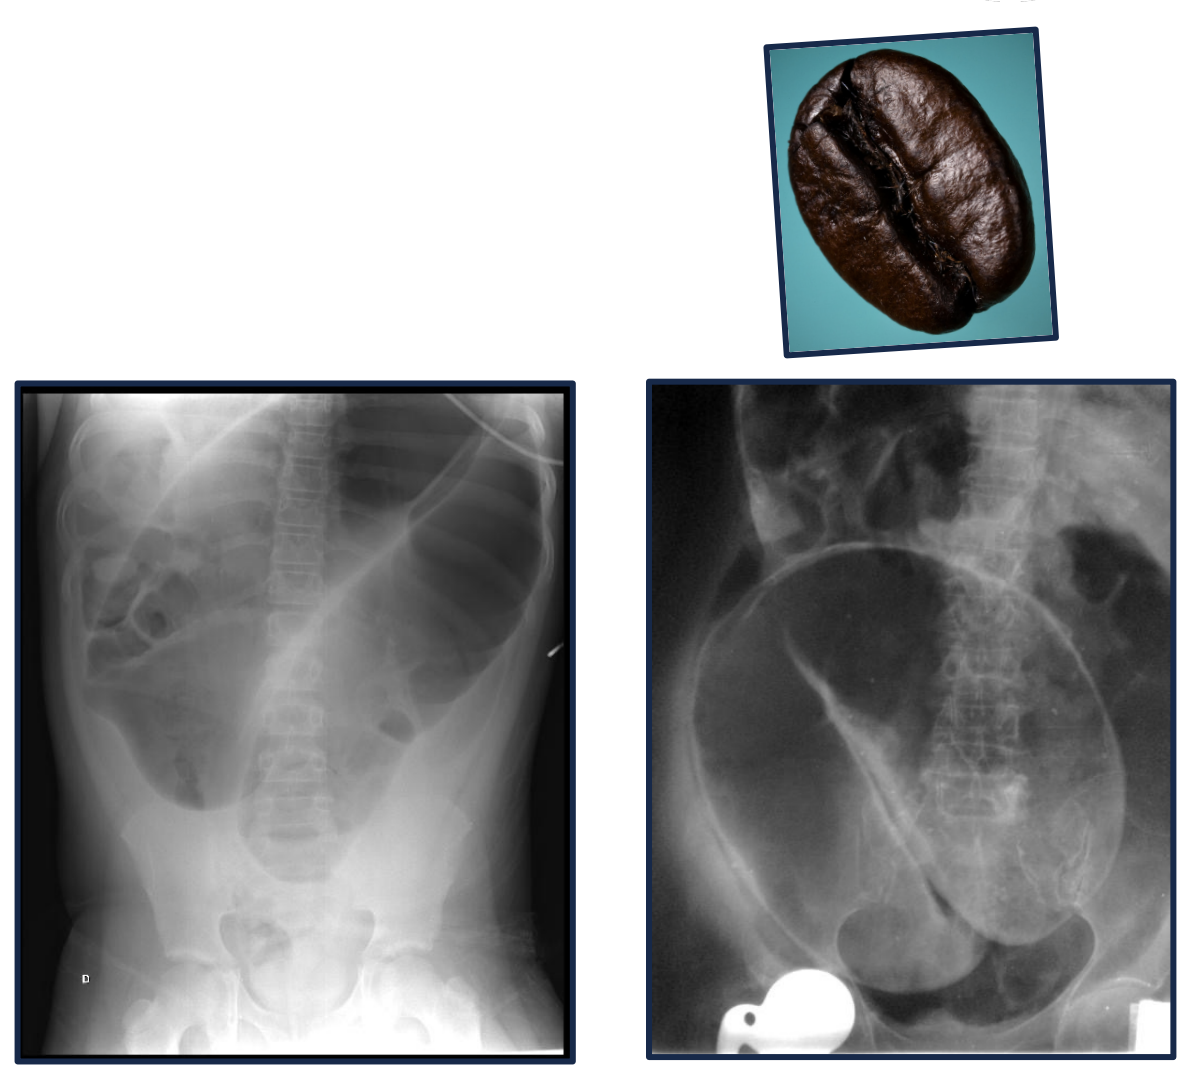

Coffee bean sign on abominal xray is pathopneumonic for _

Coffee bean sign on abominal xray is pathopneumonic for sigmoid volvulus